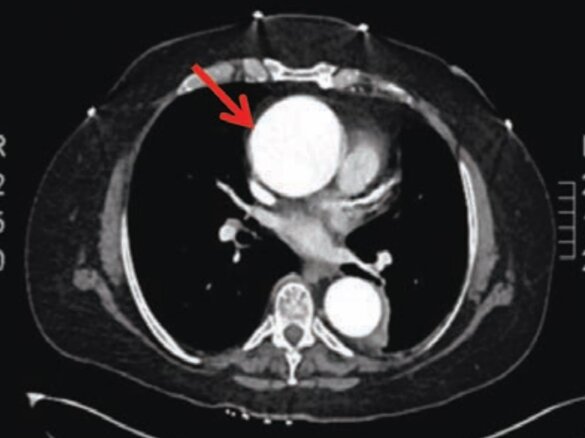

TC 3D (tomografia assiale computerizzata tridimensionale): indagine radiologica che utilizza i raggi X associati alla ricostruzione dell'immagine nelle tre dimensioni spaziali. E' una procedura che consente di ottenere immagini molto reali dell' aorta.

L'aneurisma dell’aorta e' una dilatazione pericolosa di un segmento dell' aorta nel suo tratto toracico ascendente. Tipicamente si presenta per un indebolimento della parete aortica che si dilata raggiungendo diametri anche doppi rispetto alla normalità e provocando al tempo stesso la comparsa di insufficienza aortica.